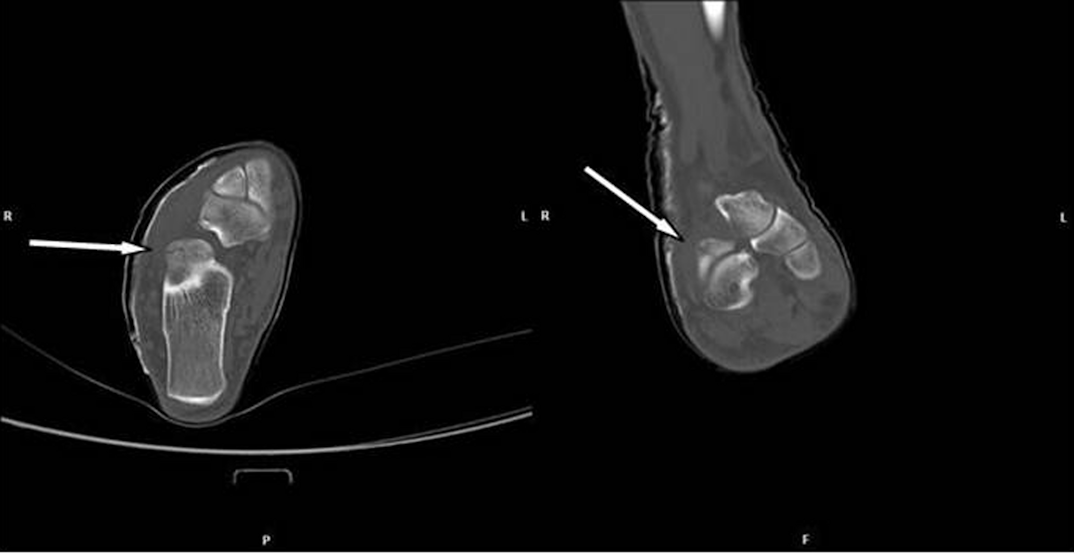

The foot with suspected fracture was imaged with conventional X-ray in two plains: axial and mediolateral (Figure 2 [Fig. 2]). However, no disruption of the bone continuity could be seen. Because of persistently pain a MRI scan was performed 10 days after trauma. There was no indication of a ligament rupture but a suspicion of a fracture of the right processus anterior calcanei. A CT scan was therefore conducted which revealed a calcaneus fracture line (Figure 3 [Fig. 3]).

Figure 3: Scan of the calcaneus with a discrete fracture without dislocation of the bone: CT taken at the initial examination. Arrays indicate the fracture lines

Six weeks later, the patient received a control examination for the healing process. To reduce radiation dose, a CBCT was performed. A thin fracture line of the calcaneus was clearly visible (Figure 4 [Fig. 4]). Some sections indicated ossification signs as proof of a healing process (Figure 4 [Fig. 4]). Hence, there was no need for a surgical approach.

Figure 4: Scans of the calcaneus with a discrete fracture without dislocation of the bone: CBCT taken 6 weeks later at a follow-up examination

CBCT easily detected a discrete fracture in the complex calcaneus. Comparing with CT, the thin fracture was more distinct in the CBCT scans although the fracture was readily in healing process and therefore should be less visible. Consequently, an even distinct imaging of the fracture could be expected by a CBCT scan at initial diagnosis.